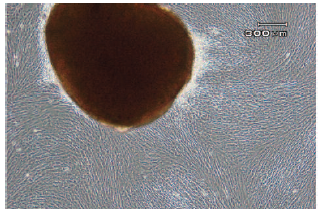

The initial growth of WJ-MSCs consisted of adherent spindle-shaped cells (Figure

1) that became confluent after an average of 21 days. Flow cytometry analyses

showed that WJ-MSCs were positive for CD90 markers and negative for CD45, CD105,

and CD34. The expression of markers was not changed after freezing (Figure 2).

Figure 1. Initial Growth of Mesenchymal Stem Cells From the Umbilical Cord Wharton Jelly Explant (×100)